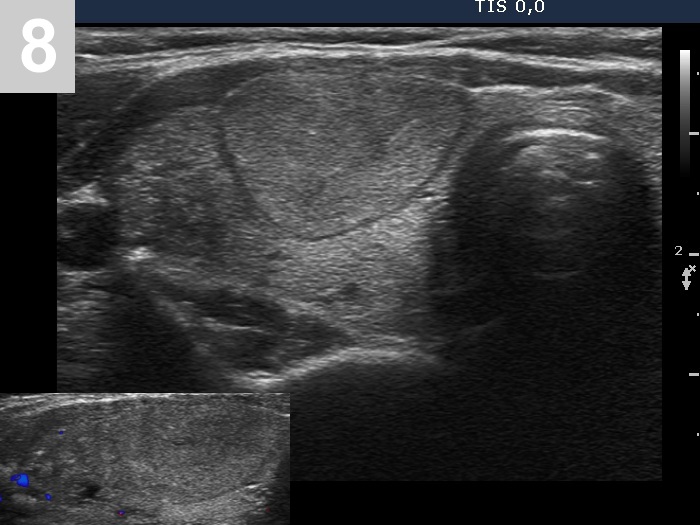

3 US of thyroid cancer

Pre- and postoperative ultrasound in thyroid cancers

Cases to be discussed on January 18, 2024